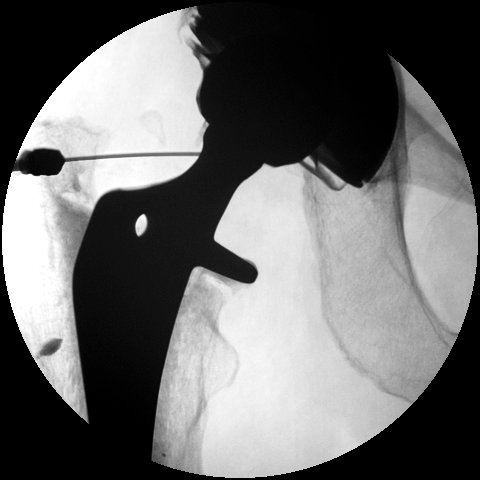

1. Infection

Peters et al J Arthroplasty 2009

Management